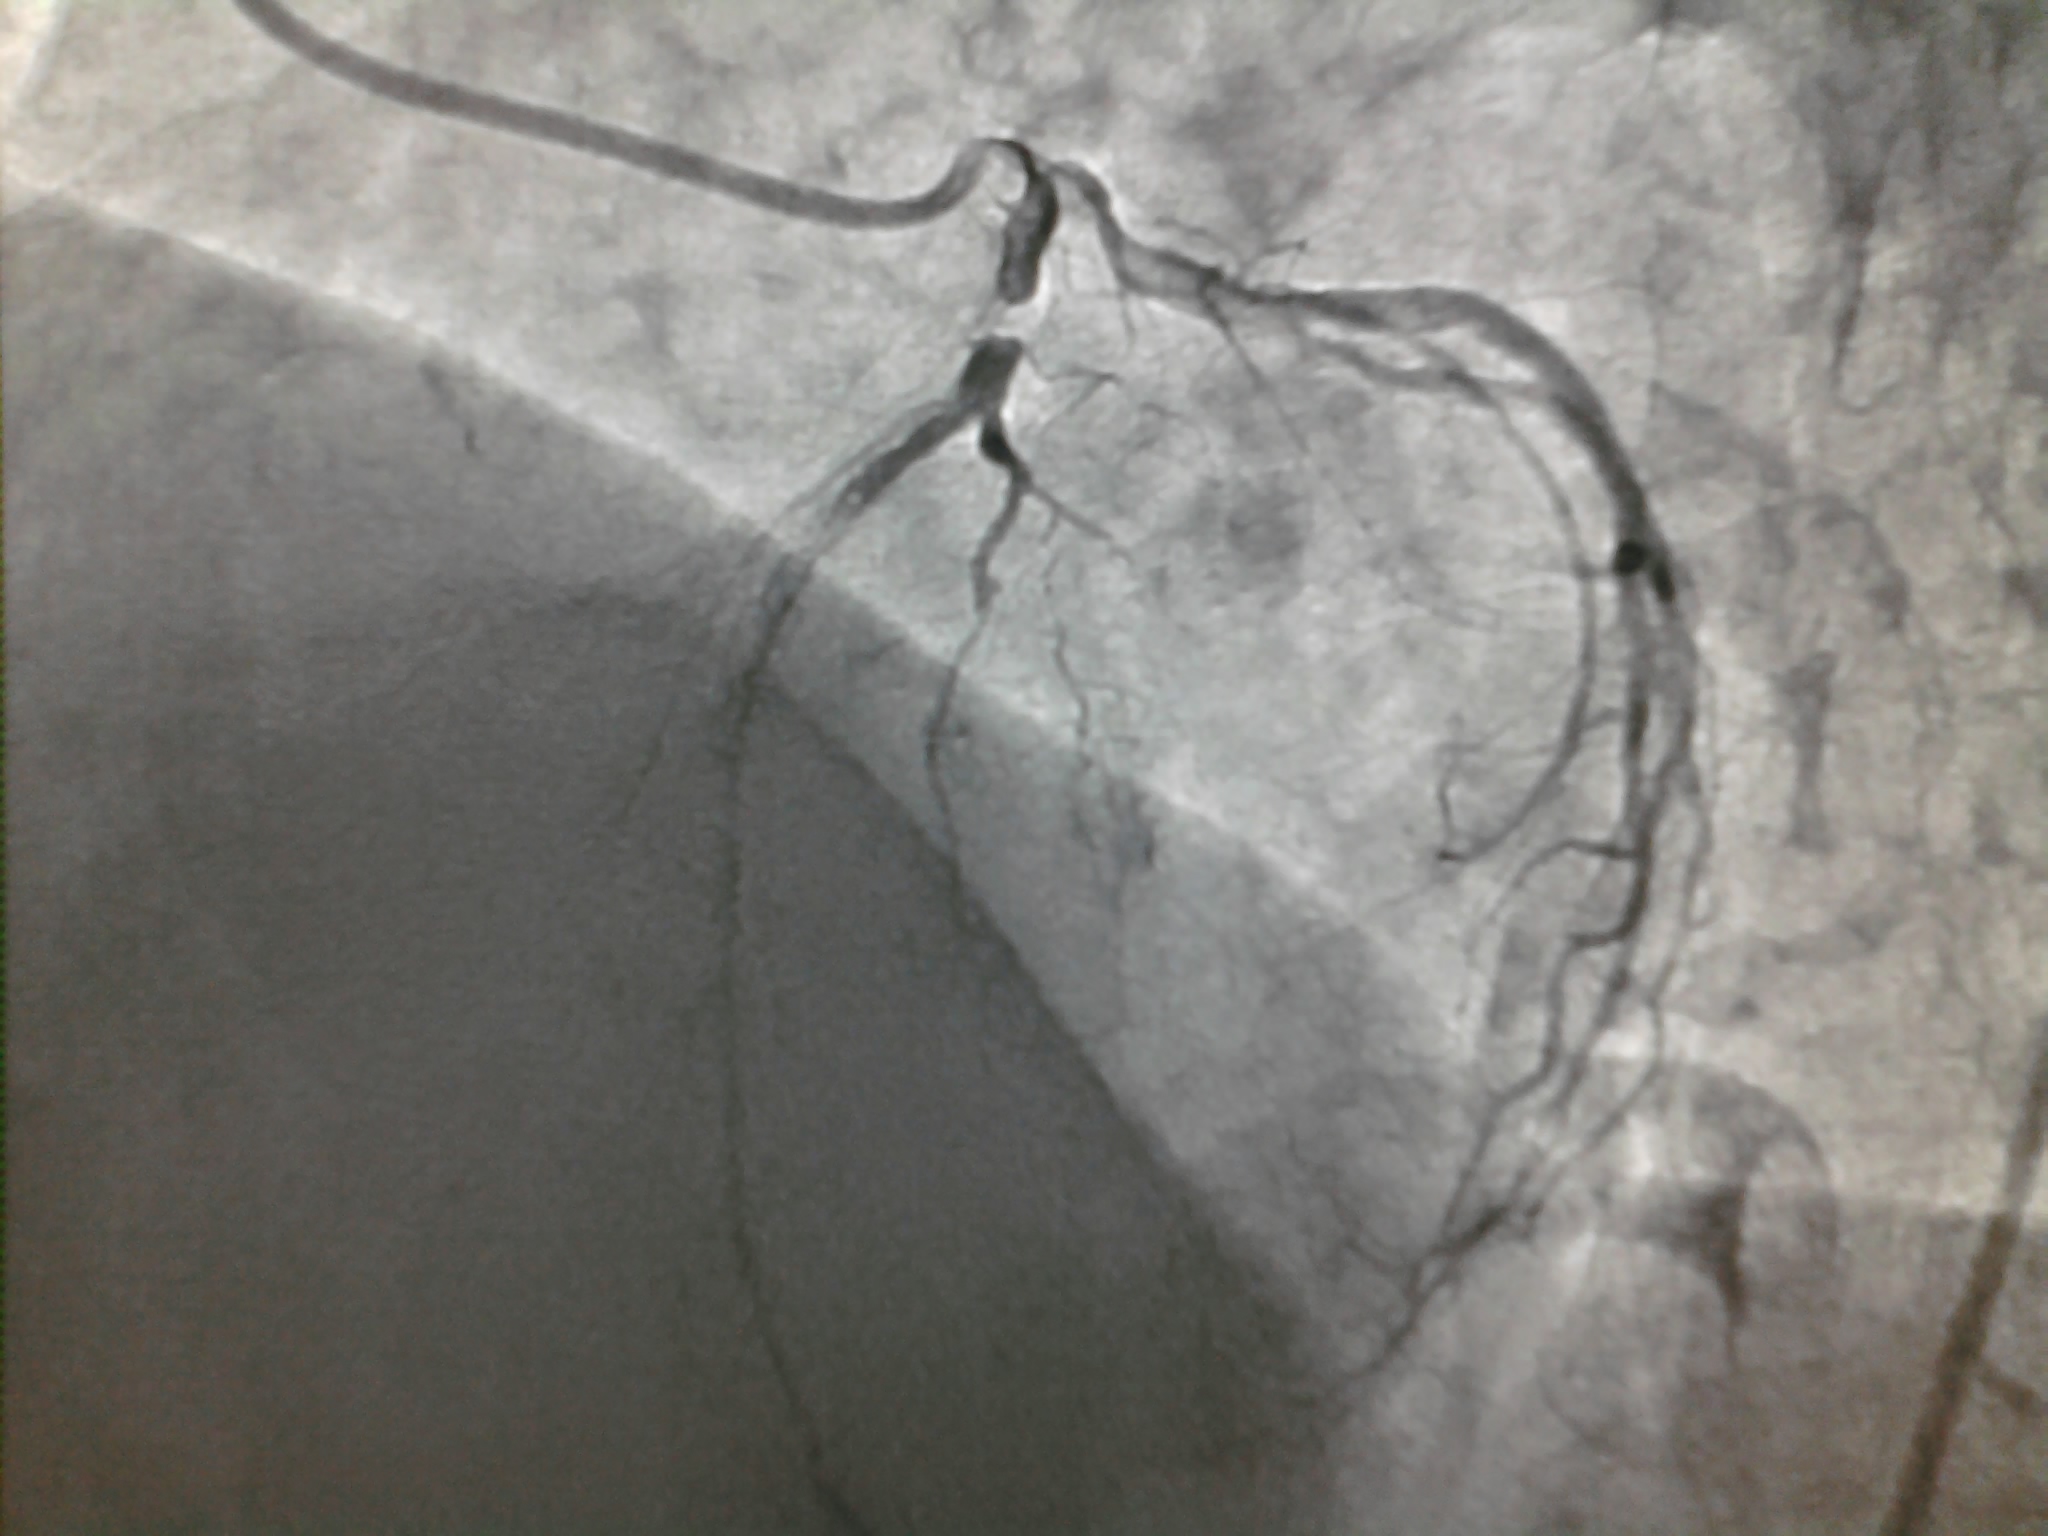

Thousands of coronary angiograms are done every day. Cardiologist no longer get excited to see exotic coronary lesions .Still , some images can be striking and dramatic. Here is an angiogram from a middle aged man with stable angina , who was one among the routine early morning diagnostic studies in our cath lab.

How this man was able to fill up the distal LAD almost completely? (With a complete cut off right in the neck of LAD )

Yes . The first one is right . An almost invisible antegrade channel doing a exemplary job !

Realize an important fact . The distal flow beyond an obstruction is not primarily dependent on degree of obstruction but the status of the distal vascular bed . If it is normal even a hair-line patency can profusely perfuse the distal myocardial segment. This is what is happening to this man with a stable angina and perfectly normal micro vascular bed.

Do not get fooled by the lay man’s logic. Realise there is no simple relation between the degree of obstruction and degree of blood flow impediment.It can be linear , curvilinear , or even inverse depending upon the evolution and timing of obstruction , number of lesions , presence or absence of collateral support , finally and most importantly the integrity of microvascular bed .